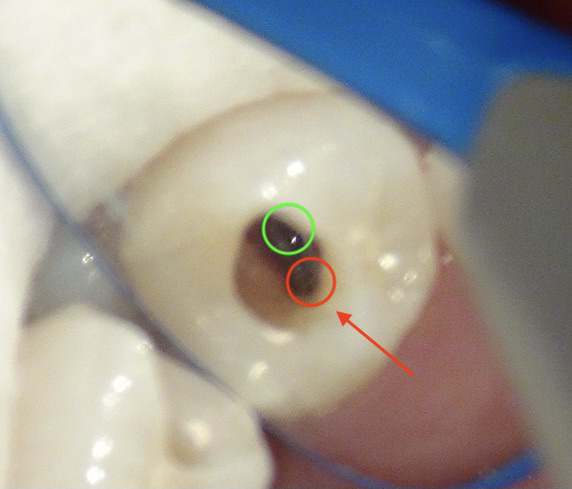

もしや‥もう一つ根管があるのかも?!

と思い、狭い歯の中を拡大していくと‥

やはりありました。もう一つの根管。

1根じゃなく2根管だったのね。

これで透過像の謎が解けました。

赤丸が2根管目。